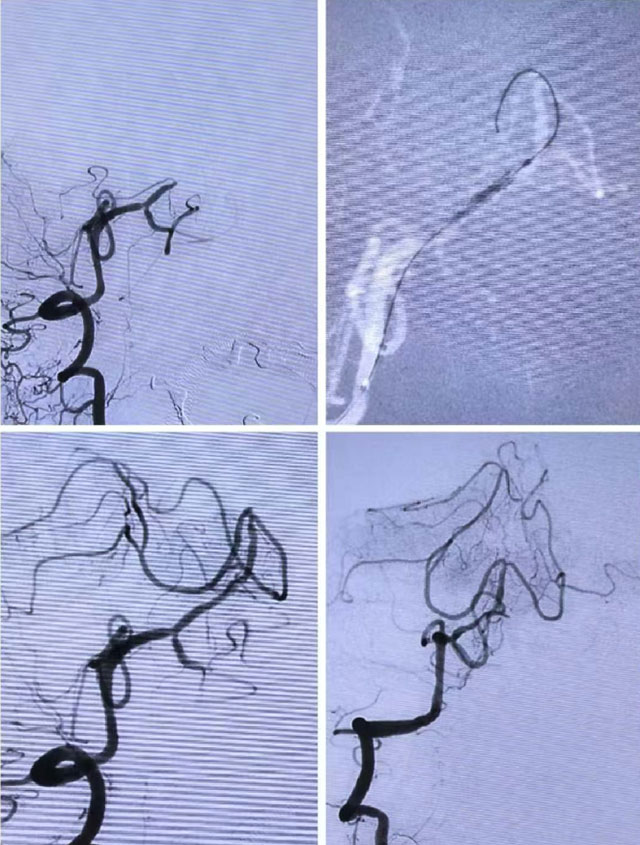

完善血管造影后,发现婆婆右侧椎动脉V2段近端扭曲,基底动脉起始段及尖端可见血栓影,双侧大脑后动脉未见显影。

立即进行血栓抽取,先后在基底动脉开口处及尖端处抽出大量暗红色血栓,基底动脉完全再通,双侧大脑后动脉及小脑上动脉显影良好。

立即为其进行脑血管造影,显示其基底动脉中段闭塞,远端未见显影(已被堵塞)。

综合评估后,郭钊云决定为万大爷实施基底动脉球囊扩张术,通过微导丝引导球囊微导管小心穿过血管闭塞处至基底动脉远端,扩张闭塞血管,抽取出血栓。

术后,血管立即恢复畅通,远端显影良好,抢救成功。

完善头部CT后,考虑为脑梗死。但由于发病超过了溶栓时间窗,进一步完善头部CTP、CTA检查,患者存在缺血半暗带,有进一步再灌注治疗指征,遂立即进行脑血管造影,发现其右侧椎动脉起始段扭曲,基底动脉中段闭塞,远端未见显影。

综合评估后,医生决定为其实施基底动脉球囊扩张+血栓抽取+支架成形术,快速开通了闭塞血管。